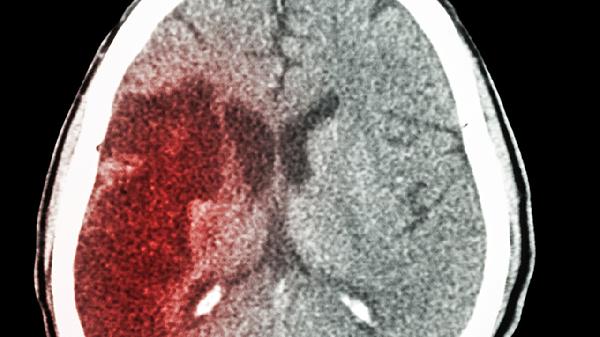

当出血发生在左侧大脑半球或脑干时,血肿直接压迫控制右侧肢体的运动神经传导束。这种情况常见于基底节区出血,患者可能出现右侧偏瘫伴肌张力增高。需通过头颅CT定位出血灶,急性期使用甘露醇注射液降低颅内压,配合甲钴胺片营养神经。若血肿量超过30毫升或出现脑疝征兆,需考虑神经内镜下血肿清除术。